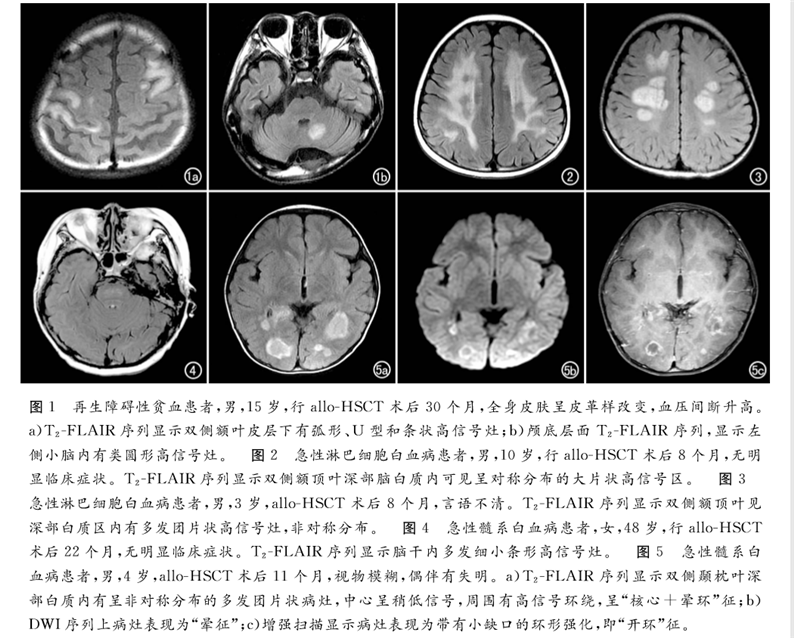

論文回顧性分析了2013年6月—2017年12月北京陸道培醫(yī)院確診為allo-HSCT后并發(fā)中樞神經系統(tǒng)慢性移植物抗宿主病的12例血液病患者的臨床和影像學資料。得出結論,MRI是發(fā)現血液病異基因造血干細胞移植(allo-HSCT)后并發(fā)中樞神經系統(tǒng)慢性移植物抗宿主病的有效手段,可以提高對本病的診斷及鑒別水平,為臨床制訂佳治療方案提供幫助。